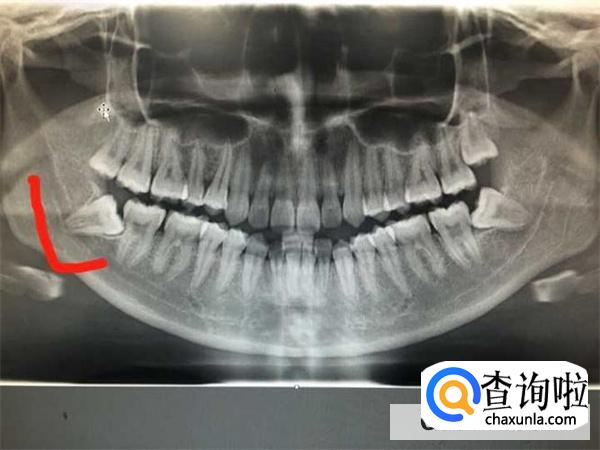

人们在生活中拔恒牙时,不会出现瘦脸的情况。所谓的拔横牙,主要是牙齿都长在颌骨上面,包括智齿,一旦人们在生活中因为种种因素的影响,此刻需要拔智齿的时候,那么就需要及时的配合医生。

一般人们在18岁的时候,智齿会随着时间的推移慢慢的出现,一旦智齿出现之后伴随红肿等等情况,此刻需要及时的拔除智齿,一般对人们的颌骨并没有太大的影响,当然也不会出现瘦脸的情况。

大众在生活中想要拔除智齿的时候应该趁早拔除,一般在40岁之前将智齿给拔除避免给人体造成严重的影响。

小伙伴在日常生活中想要拔除智齿的时候,一定要趁自己年轻及时的去口腔医院进行相关的检查,如果智齿并不太好,这时候就需要及时的将智齿拔除。

有些女性在生活中出现长智齿并且伴随怀孕,此刻因为智齿发育不良,导致众多情况产生,建议大家在生活中尽可能的拔除智齿,避免在怀孕期间出现牙齿疼痛的情况而影响众多的问题。